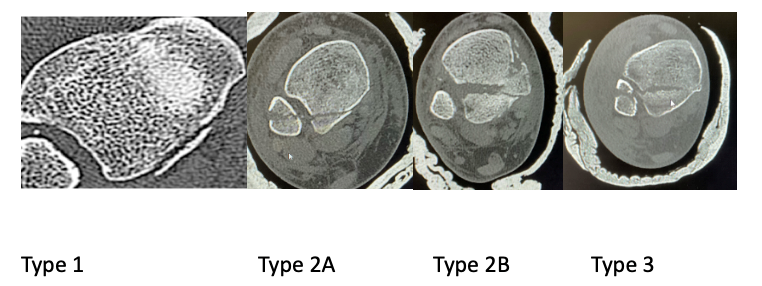

All patients presented to our department with trimalleolar ankle fractures from October 2021-March 2023 were included in the study. We excluded the patients from study who were under 18 years of age, does not require posterior malleolus fixation or need fixation method other than plate osteosynthesis. On presentation trimalleolar fractures were identified on Anterior-posterior and lateral radiographs. Patient presented with subluxation or dislocation of ankle needing manipulation were treated by the on-call team Post reduction Splinting (Back slab) was applied and radiographs were obtained to assess the reduction. Subsequently computed tomography (CT) was acquired with coronal, sagittal, axial planes, and 3D reconstruction. The fracture fragments were evaluated using Mason & Molloy classification14 and divided into subtypes 1, 2a, 2b and 3 fractures (Fig 2). Definitive fixation was delayed until the soft tissue settles. If concern with soft tissue and unstable fracture not able to maintain the position in back slab, temporary external fixation was applied until soft tissue settles. Osteosynthesis using fragment specific implant (VolitionTM) and relevant surgical approach was performed. Post operatively these patients were followed in outpatient department at 2, 6,12,26 weeks. They were clinically assessed for any pain, stiffness, infection, nerve damage, CRPS metalwork irritation or failure, and clinical union Functional assessment was carried out using The Manchester-Oxford Foot Questionnaire (MOXFQ) and Foot and ankle disability index (FADI). Anterior -posterior, lateral and mortise radiographs were taken to assess the fixation, adequacy of reduction and radiological union.

Fig2. Axial CT scan showing different types of trimalleolar fractures based on Mason and Molly Classification 36